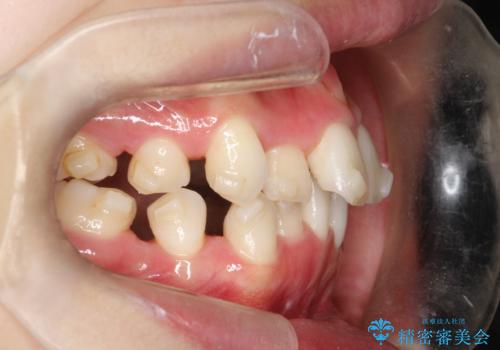

途中、臼歯の近心傾斜を認めましたが、追加アライナーを使用することでリカバリーを行いながらインビザラインのみで治療を完了することができました。